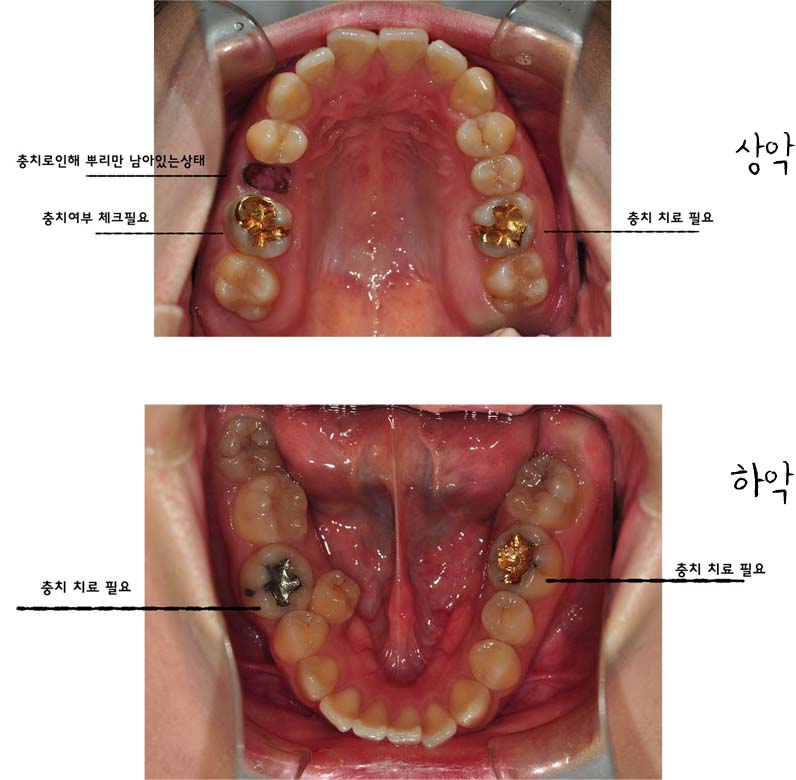

저는 치아가 덧니는 심하지 않기때문에 교정하기에 어렵지 않을거라 혼자 생각했는데 제가 잇몸과 치아 모두 돌출되어있고 어려운 케이스라고 하시더라구요 헝헝 (아래 사진을 참고해주세요~)

일단은 교정전 단계가 충치치료(충치 없으면 생략)- 발치- 치아 본뜨기- 킬본 교정기 제작 이런단계로 넘어가는데

저는 충치가 있어서 일단 어금니 위 아래 두개씩 치료를 받아야 한다고 했어요 그리고제가 안쪽 어금니에 잇몸이 많아 교정기 부착이 잘안될수 있어 잇몸을 살짝 잘라야 한다고 하더라구요